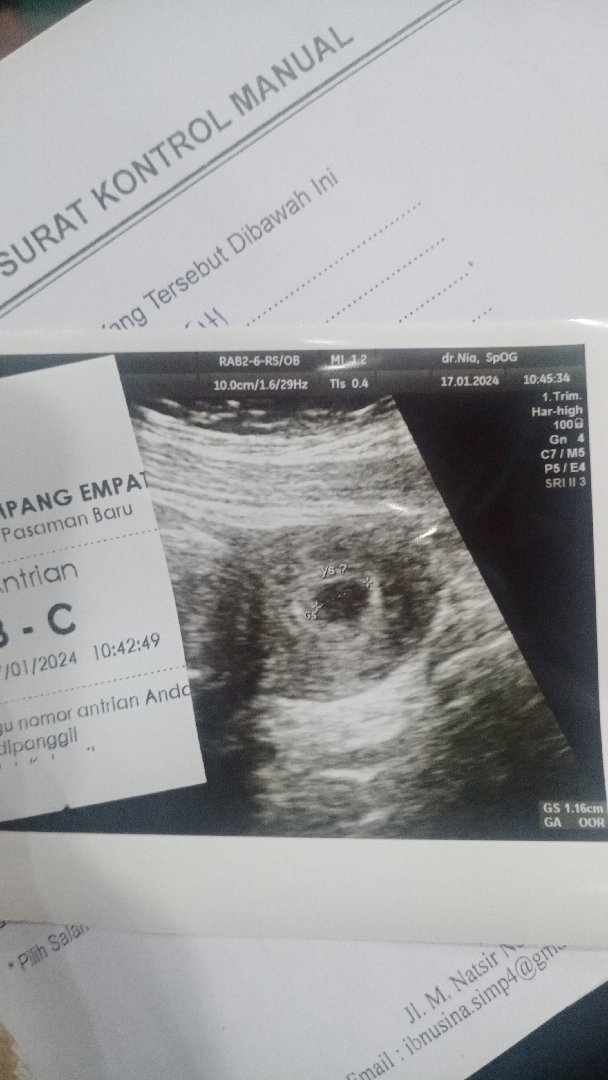

Janin belum kelihatan

Bund saya HPHT 7 desember, klo d apps kmrn 5week6hari ya, kmrn saya jdwal kntrol usg tp blm kelihatan janin nya bund, apakah normal?

Biasanya pada usia kehamilan 6 minggu keatas USG transvaginal sudah bisa terlihat gambaran kantungnya, Bunda. Namun pada usia ini seringkali janin memang belum akan tampak karena ukurannya yang masih sangat kecil, kantung biasanya terbentuk sekitar 5-7 minggu setelah menstruasi terakhir dalam siklus alami sehingga biasanya setelahnya baru terlihat janinnya.